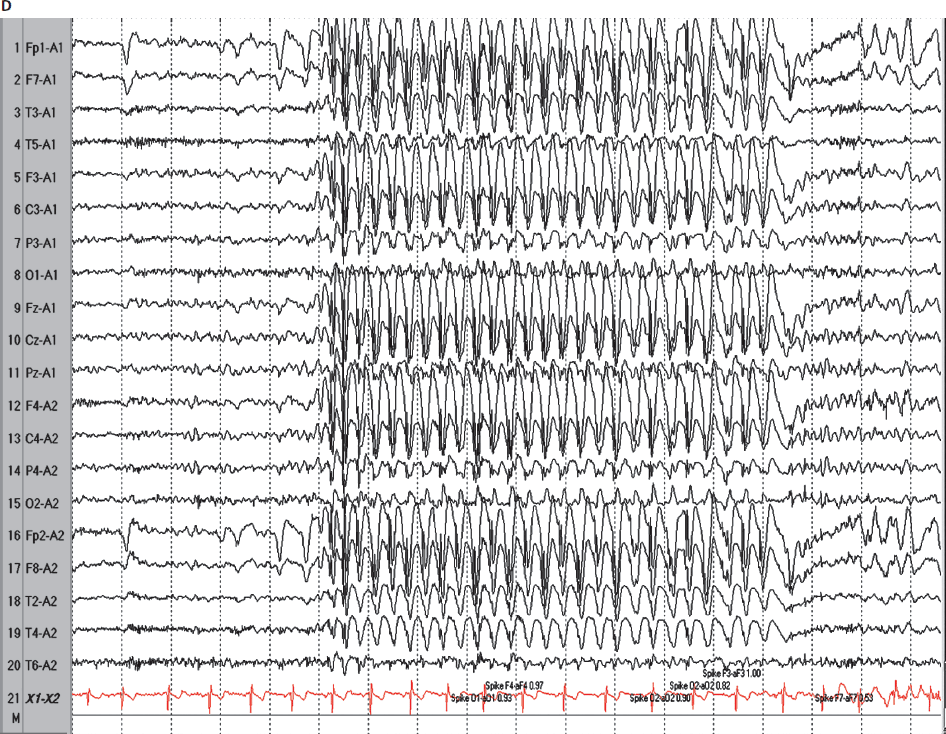

What is a tonic-clonic seizure + what does EEG show?

Losing consciousness + falling to ground T

onic phase = stiffening, 10-20s

Clonic phase = jerking 30-40s

Causes cyanosis, excessive salivation, tongue biting + incontinence

Bilateral, slow wave, subcortical seizures